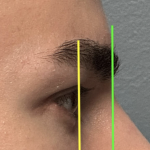

“Aesthetic temporal reduction” (often called temporal narrowing surgery) is a niche craniofacial procedure aimed at reducing the width of the head in the temple region (the area above and slightly behind the eyes). What it targets The temporal region (sides of the skull) Specifically: Temporal bone (outer skull) Temporalis muscle (a chewing muscle that can add bulk) How it’s done Read More…